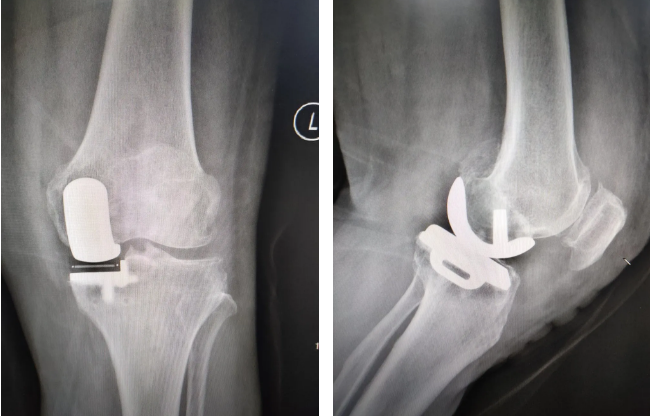

UKA术后

患者入院后,经全体组内医师讨论,仔细阅片并测量力线,结合查体及体征,分析病情,考虑病变集中在左膝前内侧间室,李主任建议行微创膝关节单髁置换术,并顺利完成。术后,患者疼痛耐受度良好,屈伸功能恢复进度理想,术后第一天即能下地行走,第五天即能顺利出院,并自行驾驶手动挡汽车返回西海岸新区家中。赵大叔对手术效果极为满意,拍摄视频表达欣喜之情。